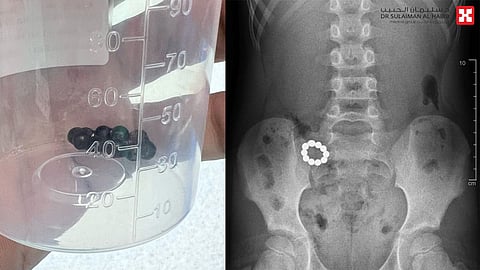

الذي قال أن الطفل أسعف إلى المستشفى وهو يعاني من إعياء شديد وآلام حادة بالبطن، مصحوبة بنوبات متكررة من القيء، وفور وصوله خضع لحزمة من الفحوصات الدقيقة كالأشعة السينية X-ray والتصوير المقطعي المحوسب Ct-scan، وأظهرت أن الأجسام الغريبة هي "10" كرات مغناطيسية وتسببت بفعل خاصية التجاذب والتنافر في حدوث تلف وثقوب في جدار المعدة والقولون.

وأضاف د. عبدالله عبدالدائم أن الفريق الطبي سارع بوضع خطة علاجية متكاملة، وأجرى عملية عاجلة، باستخدام المنظار الجراحي لإزالة الكرات المغناطيسية ومعالجة الثقوب الناتجة عن التجاذب المغناطيسي واستئصال الجزء التالف من الأمعاء وإعادة توصيل الأجزاء السليمة، من خلال فتحة جراحية صغيرة، واستمرت العملية لنحو "4" ساعات، وتكللت ولله الحمد بالنجاح التام، ودون أية مضاعفات، ونقل الطفل بمؤشرات حيوية مستقرة إلى العناية المركزة حيث أمضى قيد المراقبة الطبية لمدة "48"، ومن ثم حُول إلى غرفة التنويم، وتحسنت حالته مع الرعاية الطبية الحثيثة، وبدأ في تناول الطعام بشكل تدريجي، وغادر بعد "5" بصحة ممتازة، واستعاد لاحقاً نمط حياته الطبيعية.